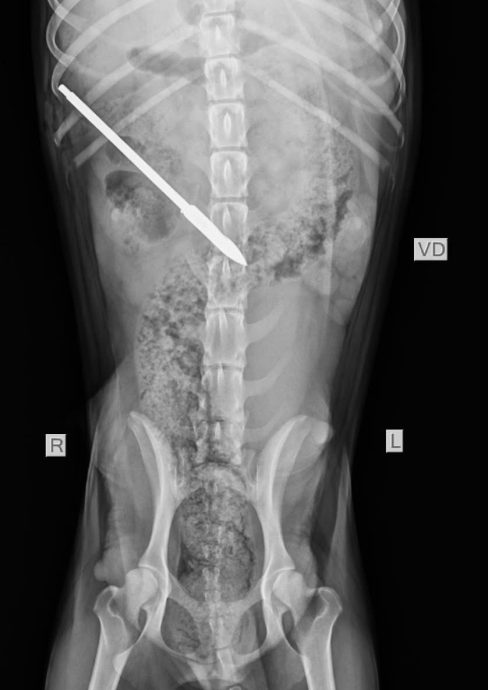

母狗哺乳中被鱼叉枪射击 刺穿肾脏击中腹主动脉

(兵南邦22日讯)一只正在哺乳的流浪母狗,竟被人用鱼叉枪射击,刺穿它的一个肾脏,并击中腹主动脉。

接获投报的婆罗洲动物福利会(Borneo Animal welfare society)负责人特蕾西受联时指出,小黑接受检查及手术后,钢矛已被顺利取出。